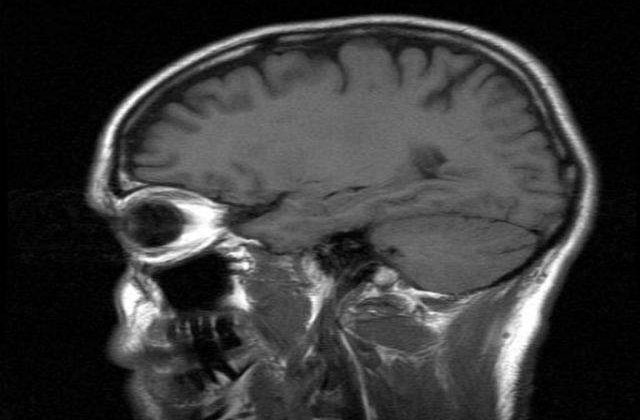

Oamenii de stiinta cred ca exercitiile fizice, atunci cand sunt practicate cu regularitate, asigura un flux constant de sange bogat in oxigen catre creier.

Astfel, se previne crearea placilor proteice - depozite de proteine din creier - care declanseaza boala.